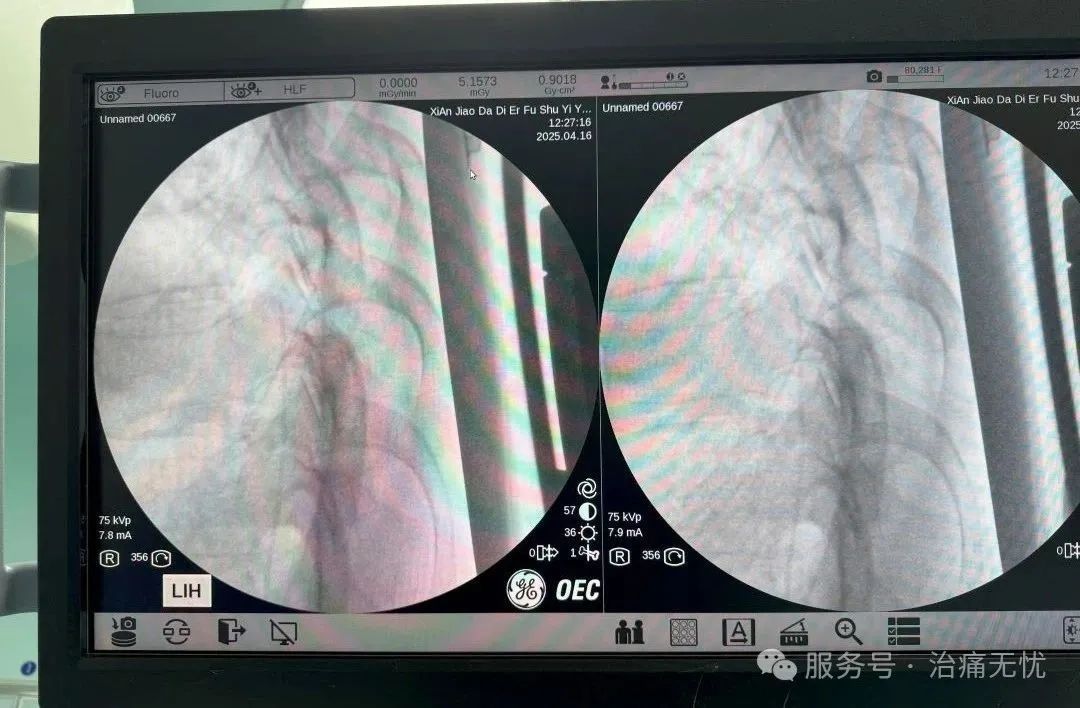

经过精密计算,将原先180mg/d的口服吗啡剂量转换为0.6mg/d的鞘内给药,通过0.3ml/h的精准输注,实现了"四两拨千斤"的镇痛效果。